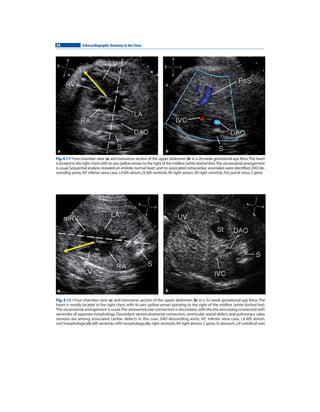

海外ブランドアウトレット通 in Anatomy Echocardiographic Amazon.com: the Store Kindle H.: Norman Silverman, Gianni, Botta, C., Andrew Cook, Enrico, Chiappa, : eBook Fetus 洋書

海外ブランドアウトレット通 in Anatomy Echocardiographic Amazon.com: the Store Kindle H.: Norman Silverman, Gianni, Botta, C., Andrew Cook, Enrico, Chiappa, : eBook Fetus 洋書

Amazon.com: Echocardiographic Anatomy in the Fetus eBook : Chiappa, Enrico, Cook, Andrew C., Botta, Gianni, Silverman, Norman H.: Kindle Store,

Amazon.com: Echocardiographic Anatomy in the Fetus eBook : Chiappa, Enrico, Cook, Andrew C., Botta, Gianni, Silverman, Norman H.: Kindle Store, Amazon.com: Echocardiographic Anatomy in the Fetus: 9788847005723: Chiappa, Enrico, Cook, Andrew C., Botta, Gianni, Silverman, Norman H.: Libros,

Amazon.com: Echocardiographic Anatomy in the Fetus: 9788847005723: Chiappa, Enrico, Cook, Andrew C., Botta, Gianni, Silverman, Norman H.: Libros, Echocardiographic anatomy in the fetus 2009 pg | PDF,

Echocardiographic anatomy in the fetus 2009 pg | PDF, Echocardiographic anatomy in the fetus 2009 pg | PDF,

Echocardiographic anatomy in the fetus 2009 pg | PDF, Echocardiographic anatomy in the fetus 2009 pg | PDF